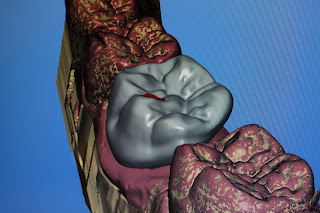

| Modellation der Implantatkrone am Computer |

Anschließend wird mit dem Computer die Implantatkrone konstruiert. Mit dem CEREC 3D- System funktioniert die dreidimensionale Darstellung und Konstruktion der Implantatkronen, da hier auch die benachbarten Zähne dreidimensional dargestellt werden, kann die Restauration optimal gestaltet werden. Die neue Implantatkrone wird so den anatomischen Besonderheiten der Nachbarzähne angepasst, und garantiert dem Patienten einen hohen Komfort.

| Computermodellation der Implantatkrone |

Der computergesteuerte Mini-Roboter schleift die Keramikkrone vollautomatisch innerhalb weniger Minuten aus einem Glaßkeramikblock heraus. Die sehr ästhetische Krone kann jetzt sofort beim Patienten angepasst und eingesetzt werden.